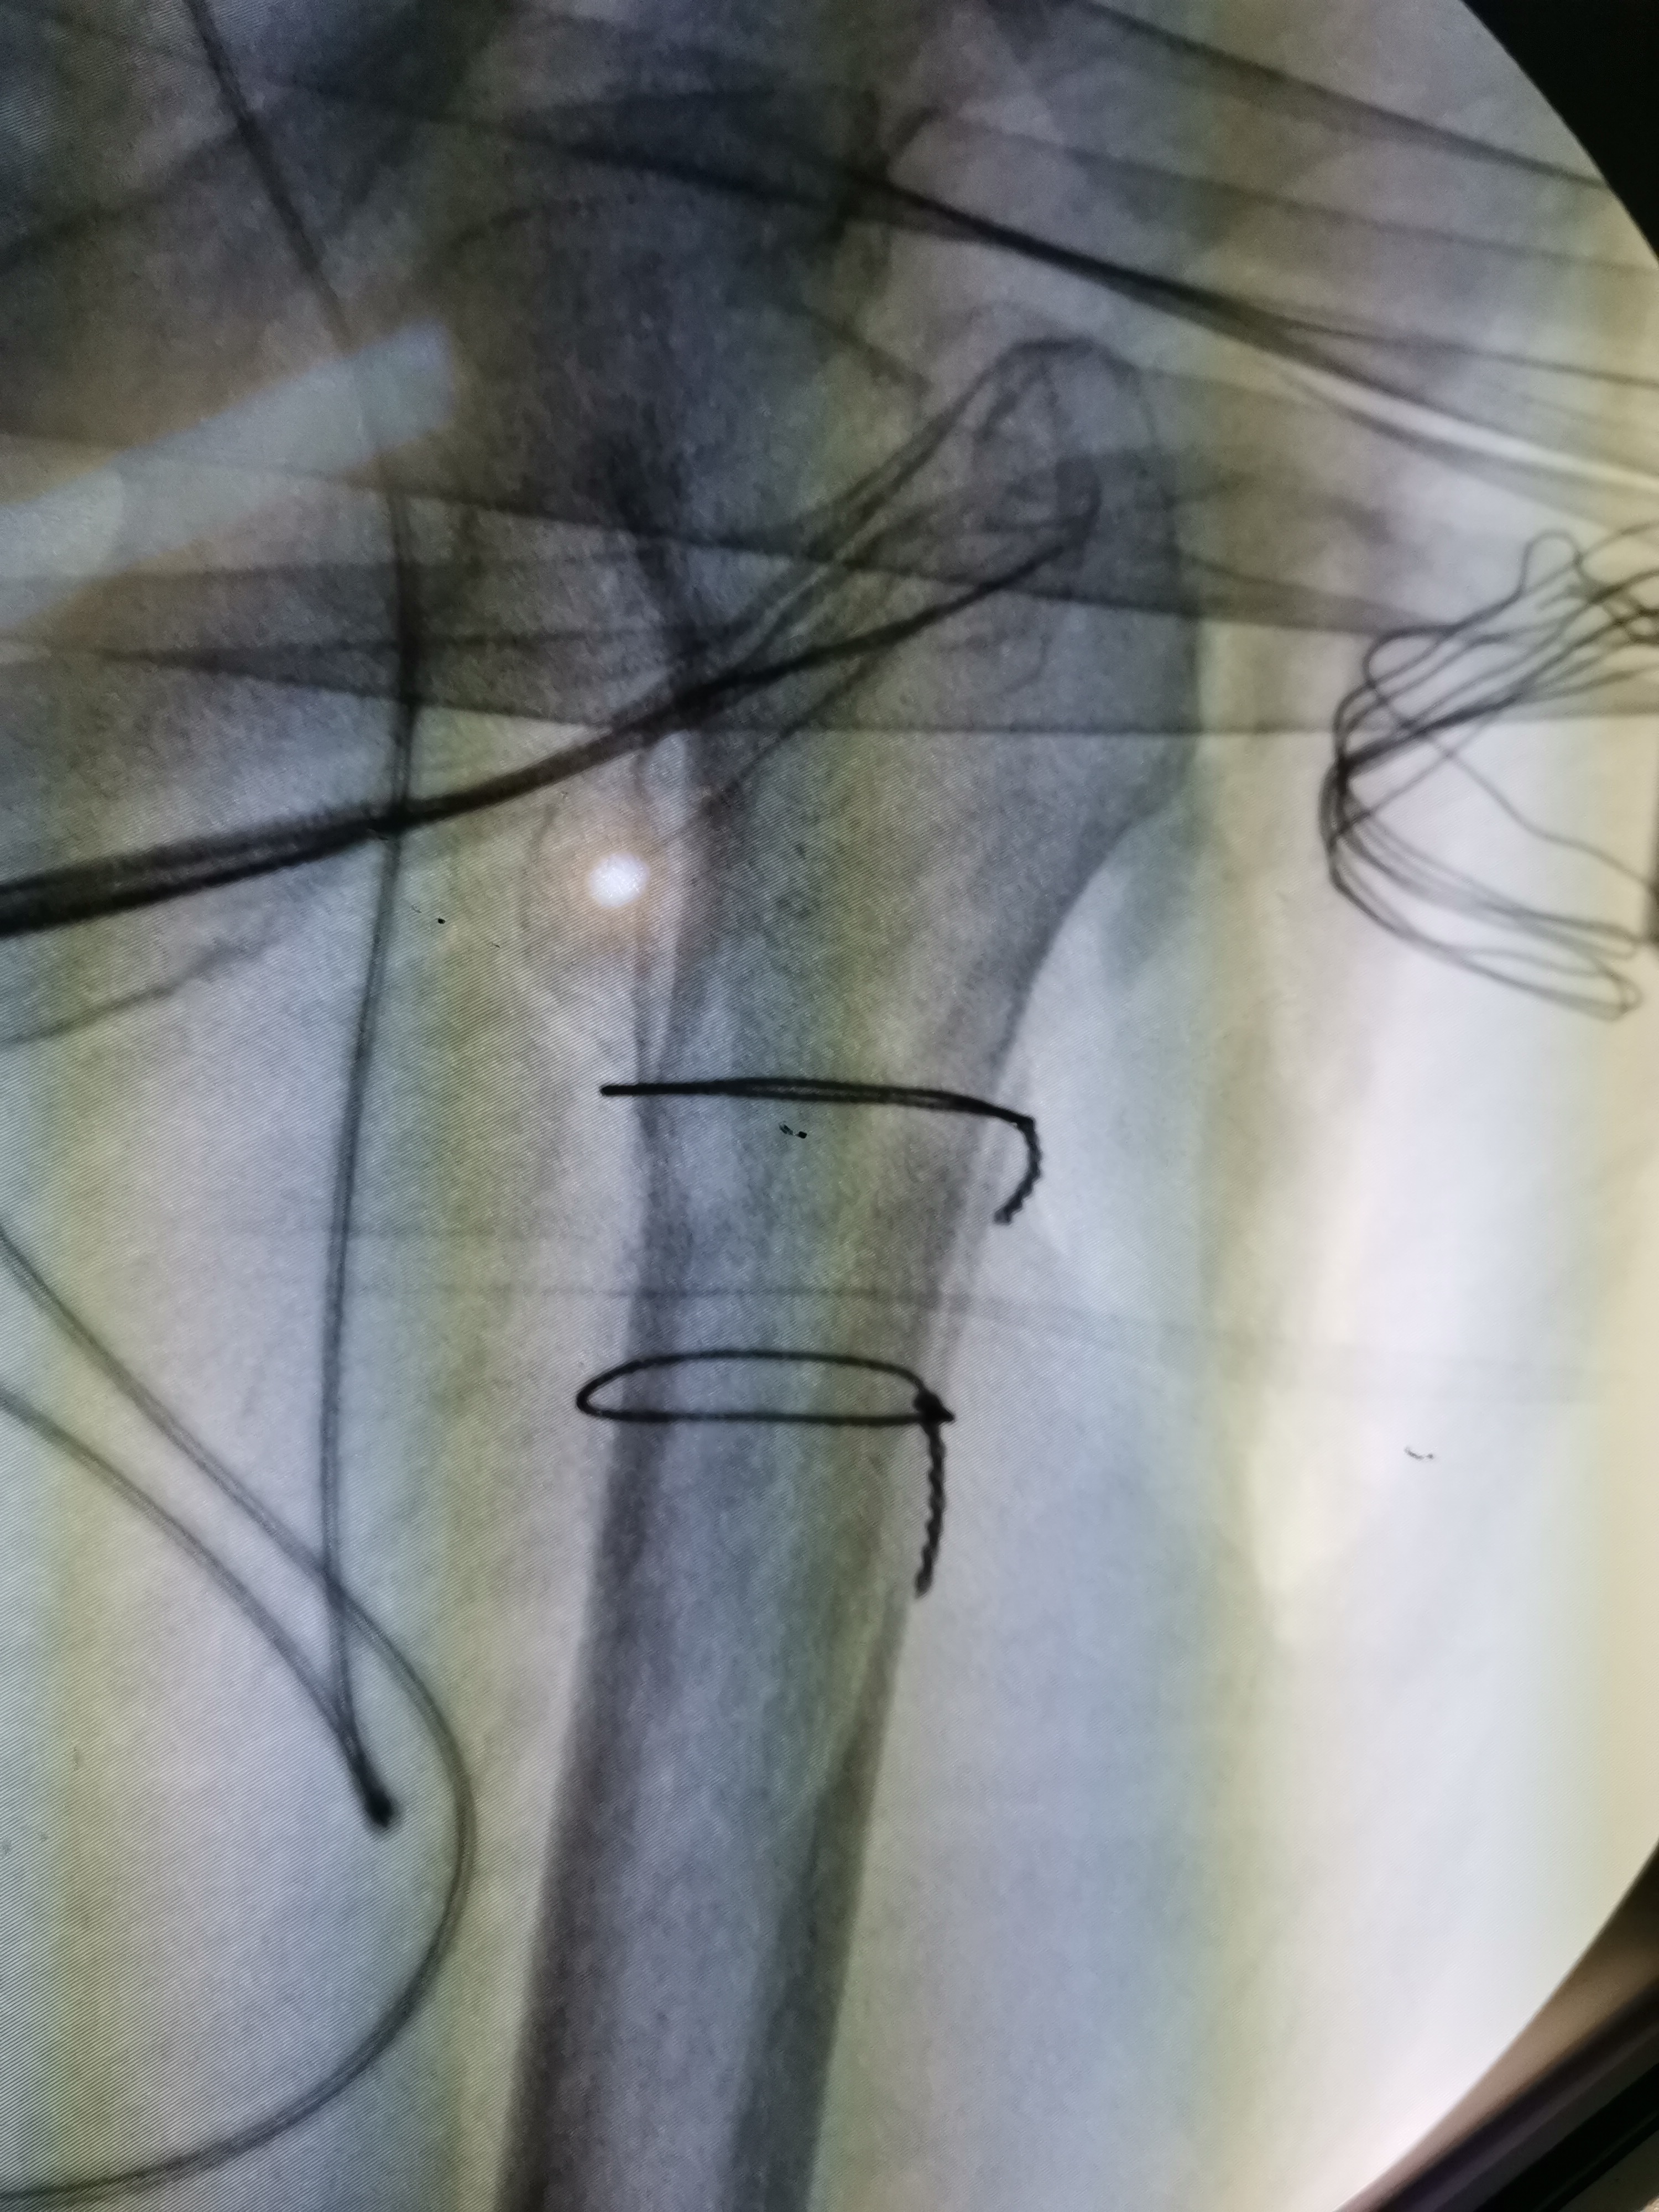

手法复位成功可以大大减少手术时间,避免皮肤切开后老人一边流血一边复位,从而增加出血量。在手法复位后,可以使用可移动的X线机进行透视,查看复位的情况,如下图所示,复位基本满意后就可以开始手术:

复位前后比较